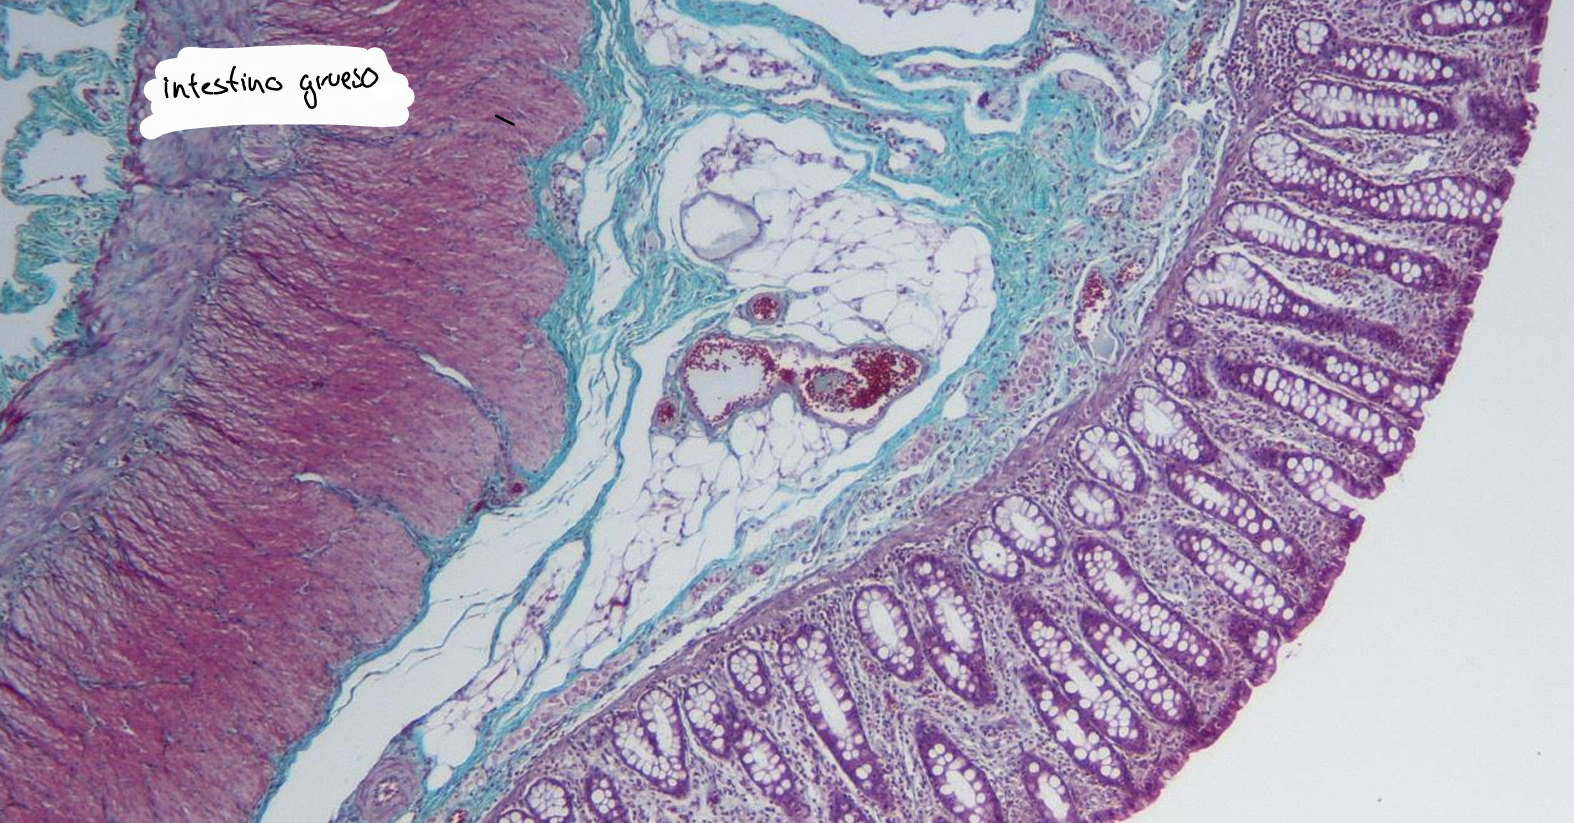

intestino grueso es la parte final del sistema digestivo, encargada de absorber agua y electrolitos, además de formar y eliminar las heces.

intestino grueso